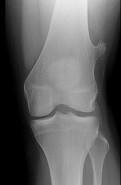

问题 女性,39岁。发现左大腿下段后部有一包块,质较硬,无明显疼痛感觉,请结合所提供的图像,选择最佳选項()

选项 A.软骨肉瘤 B.软骨瘤 C.骨肉瘤 D.骨软骨瘤 E.骨瘤

答案 D